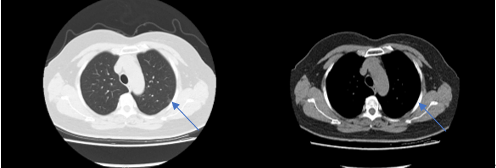

吴阿姨的CT检查提示左上肺直径约1cm的肺结节